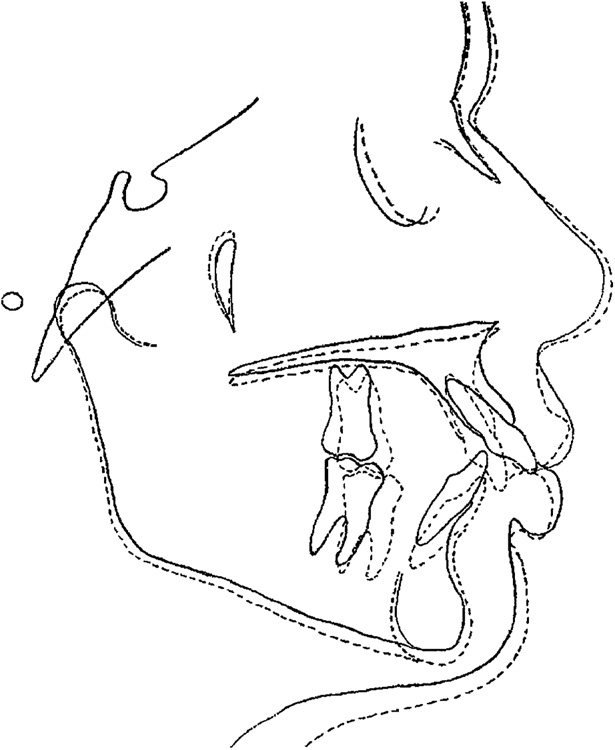

Fig 7. Cephalometric tracings superimposed on the sella-nasion plane at sella. Pretreatment, solid lines; posttreatment, dashed lines.

labial proclinations. But even with these compensatory mechanics, anterior guidance was compromised because of the tooth-size discrepancy.8 Therefore, group function was obtained in lateral excursions. During protrusion, the anterior teeth discluded the posterior teeth. A significant improvement in facial and dental esthetics was produced, despite the absence of a mandibular incisor. The cephalometric superimposition shows

the improved maxillomandibular relationship and compensated incisor position8 (Figs 7-9). The premolar extractions and the use of headgear, Class II elastics, and anterior stripping produced favorable uprighting of the maxillary incisors. There were increases in the facial angles and facial height (FMA, SN.Occl, SN.GoGn, LAFH, and LPFH). The mandibular incisors showed slight labial tipping, probably from the Class II elastics when closing the interproximal spaces. These small dentoalveolar changes also produced favorable soft-tissue changes (Fig 4).

Fig 8. Cephalometric tracings of the mandible superimposed on the mandibular plane at menton. Pretreatment, solid lines; posttreatment, dashed lines.

Fig 9. Cephalometric tracings of the maxilla superimposed on the palatal plane at ANS. Pretreatment, solid lines; posttreatment, dashed lines.